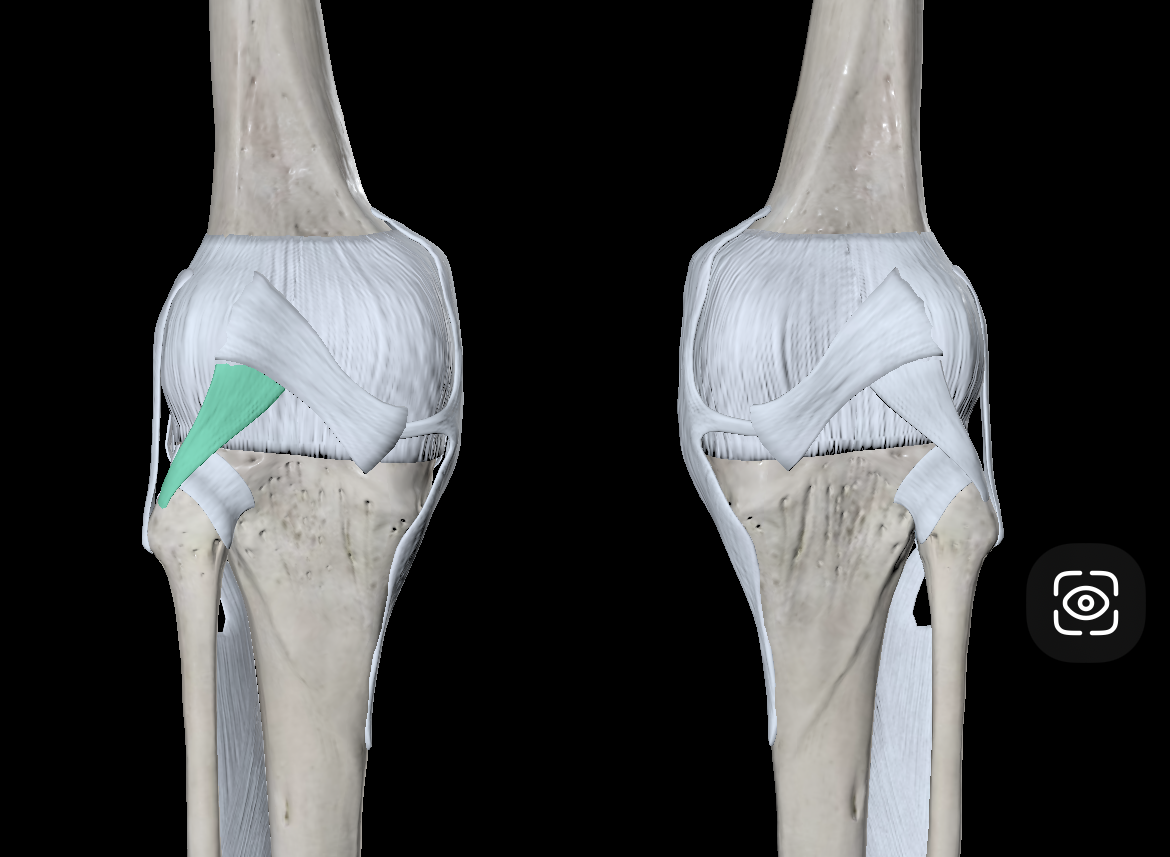

Fibular/Lateral Collateral Ligament

Tibial/Medial Collateral Ligament

Oblique Popliteal Ligament

Arcuate Popliteal Ligament

Anterior Cruciate Ligament

Posterior Cruciate Ligament